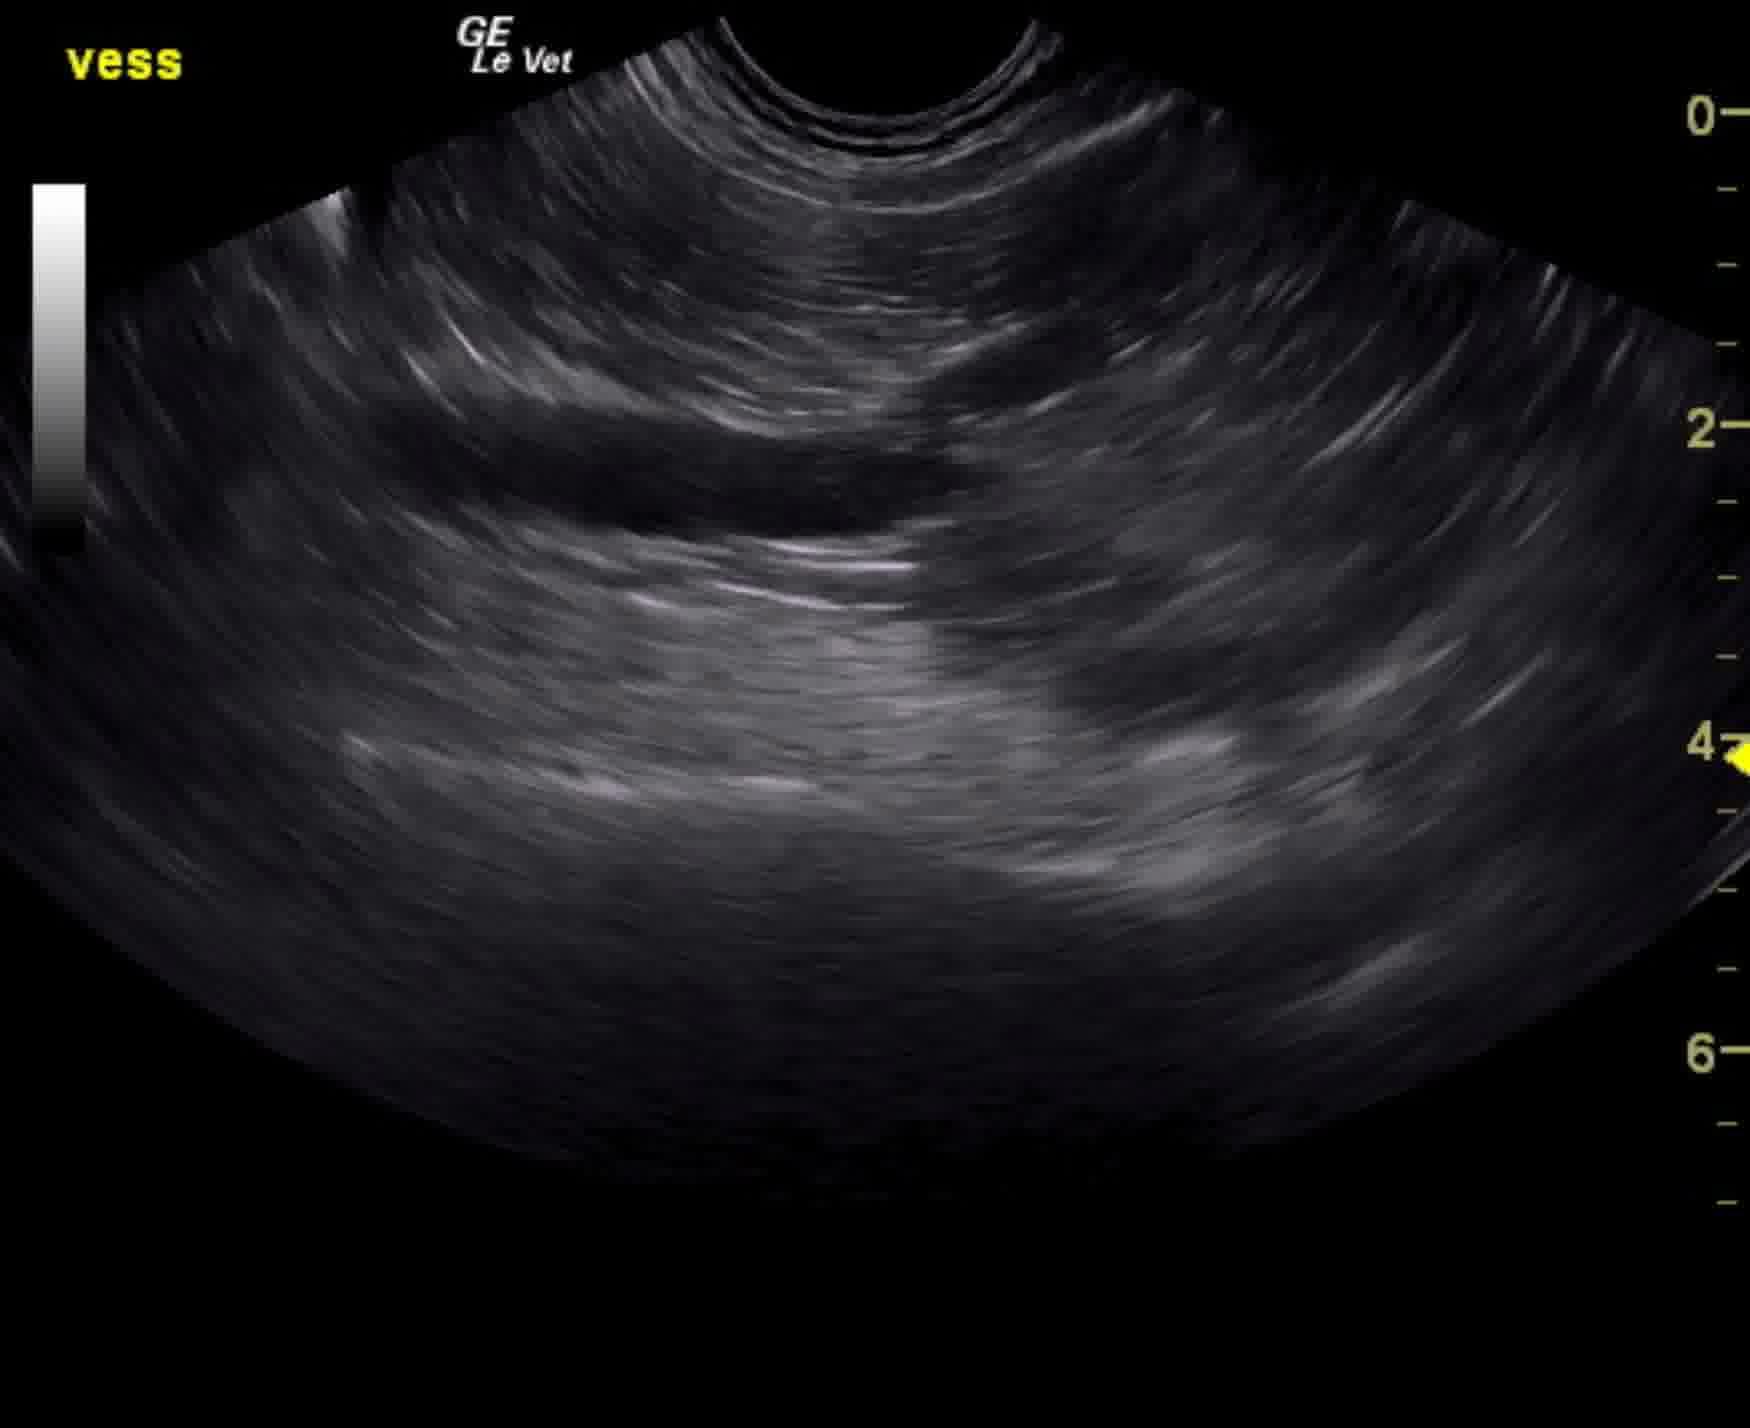

The prostate in this patient revealed a mixed, hypoechoic and multifocally mineralizing mass that measured 2.5 cm. Ultrasound-guided FNA or traumatic catheterization is recommended for confirmation. Pericapsular inflammatory pattern was noted around the prostate with proliferative tissue noted cranial to the point of the cystourethral junction.

sebastian_dimurro_beagle_6_yr_prostatic_carcinoma_2vlcsnap-2015-12-25-12h06m00s138